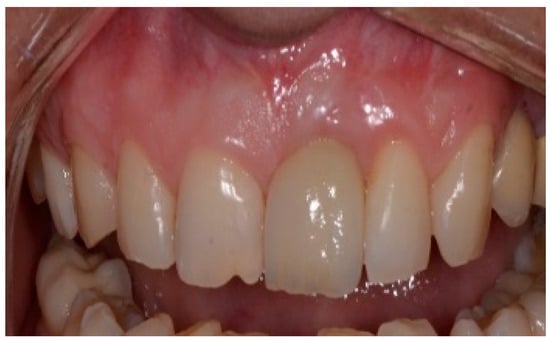

Following a 6-month healing period (Figure 6), definitive prosthetic rehabilitation was carried out using zirconia CAD CAM abutments (Straumann, Andover, MA 01810, USA). The ceramic zirconia crowns of teeth 8 and 9 were placed (Figure 7). At the two-year follow-up examination for patients #1 and #3 and three-year for patients #2 and #4, the implants were fully osseointegrated, presenting satisfactory functional and esthetic conditions without clinical or radiographic signs of any pathology.

Figure 6.

Clinical view of the implant site before final restoration.

Figure 7.

Clinical view of final ceramic crowns on teeth 8 and 9.